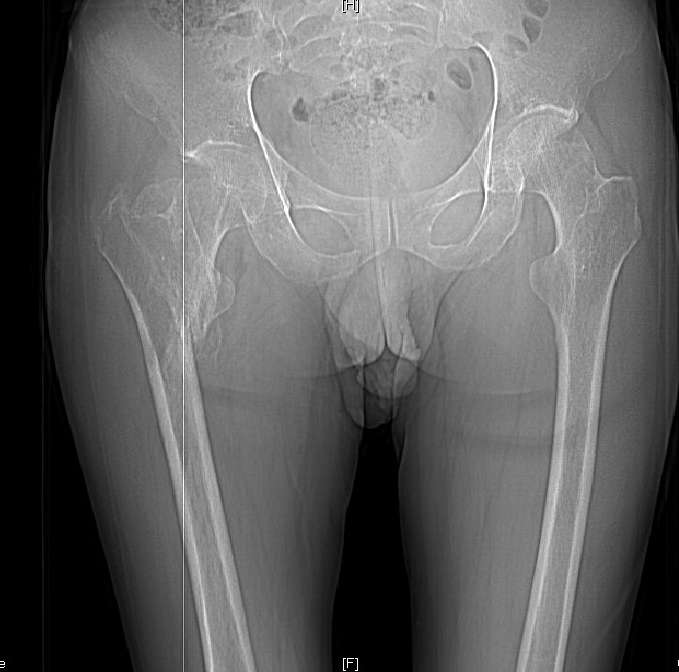

Доброго времени суток, уважаемые коллеги! Больному 45 лет. Лечили в сельской больнице на скелетном вытяжении 6 нед. по поводу межвертельного перелома бедренной кости с последующим наложением кокситной повязки еще на 2 мес.

С момента травмы прошло 5 месяцев, ходит с костылями без нагрузки, контрактуры в коленном и в тазобедренном суставах. Снимки во вложении. У нас мнения разделились. Показанием для открытого остеосинтеза мы считаем неустраненное ротационное смешение дистального фрагмента, которое может привести к нарушению биомеханики в тазобедренном суставе с последющими вытекающими последствиями.

ЭОП на сегодняшний день недоступен нам, а остеосинтез угловыми пластинами, что можно попытаться, имеет определенный риск. Как быть? Начать разработку в суставах и активизировать больного, что не было сделано до этого, или всё-таки оперировать? Будем рады Вашим советам.